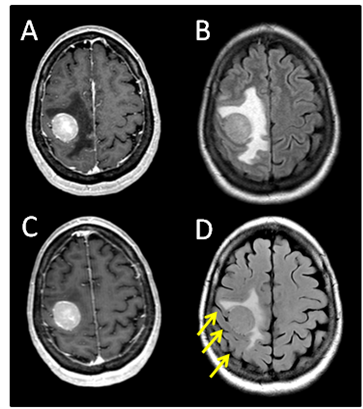

After SRS, the patient continued to have very mild, stable, left hand weakness. Her first follow up brain MRI on September 25, 2012 (4.5 weeks after SRS) showed good initial response (Figure 3B). Approximately 4weeks after SRS, however, she became more symptomatic from the intra-thoracic disease and subsequently received palliative radiation to the right hilar mass with a total dose of 30Gy in 10 fractions. She had excellent response to the chest radiation, both radiologically and symptomatically. She was then started on systemic therapy with vemurafenib.

Figure 3 Serial T1 with contrast MRI scans. (A) Pre-SRS. (B) 5 weeks post SRS. (C) 9 weeks post SRS showing the tumor to be largely necrotic, though with increased edema (arrows). (D) 5 months post SRS showing near complete resolution of contrast enhancement and edema.

The patient did well until October 23, 2012 (2months after her SRS) when she developed 2 episodes of seizure activity involving her left arm and hand without loss of consciousness. A brain MRI demonstrated increased vasogenic edema around the previously irradiated, right posterior frontal lobe lesion. The tumor had become largely necrotic (Figure 3C). There was no interval development of new metastatic foci. She was started on levetiracetam and was also given dexamethasone for the treatment of possible radiation related brain edema, which was eventually, successfully weaned off without problems. She has subsequently remained seizure free. Neurologically, she was doing well with mild residual impairment of fine motor function in her left fingers, but free of other neurologic deficits. Her overall functional status had also remained stable at ECOG 1. She was last seen in radiation oncology clinic on January 25, 2013 (5months after SRS) and was noted to be doing well. Brain MRI showed near complete resolution of the contrast enhancement and vasogenic edema of the brain lesion Figure 3D.